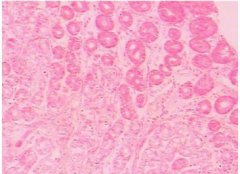

十二指腸炎是指發(fā)生于十二指腸的炎癥,分為原發(fā)性和繼發(fā)性兩種,原發(fā)性者也稱非特異性十二指腸炎。本病臨床癥狀缺乏特征性,主要表現(xiàn)為上腹部疼痛、惡心、嘔吐、嘔血和黑便,有時和十...